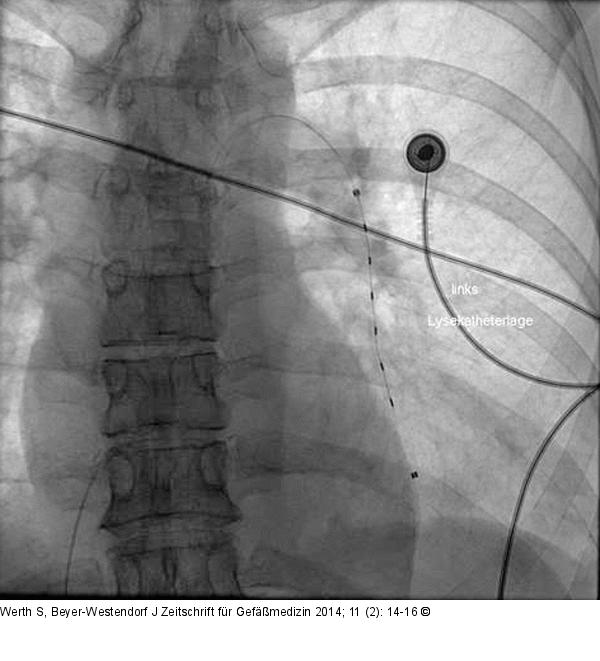

Abbildung 2: Lysekatheter Platzierung des EKOS-Lysekatheters in die Pulmonalarterie im linken Unterlappen. |

Platzierung des EKOS-Lysekatheters in die Pulmonalarterie im linken Unterlappen. |